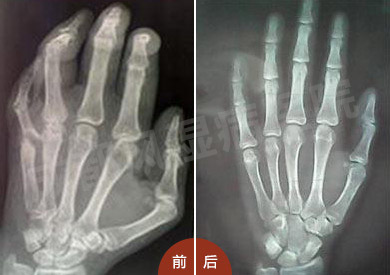

(图:患者治疗前后手部CT对比)

经过个体化治疗三个疗程后恢复健康

经过治疗半个月后:陈女士的关节疼痛有所缓解,且右肘关节可伸直,下蹲困难较前有所改善。

治疗两个月后:陈女士来院接受复诊,发现关节基本无疼痛现象,下蹲自如,复查血常规示:血红蛋白:132g/L,血小板示:293 *10∧9/L,血沉40mm/h ,各项炎性指标均较前好转。

治疗三个月后:来院复查,HD-热层析检测显示,患者各关节炎症消除,关节无疼痛感,微血管功能状态良好,已经恢复健康。